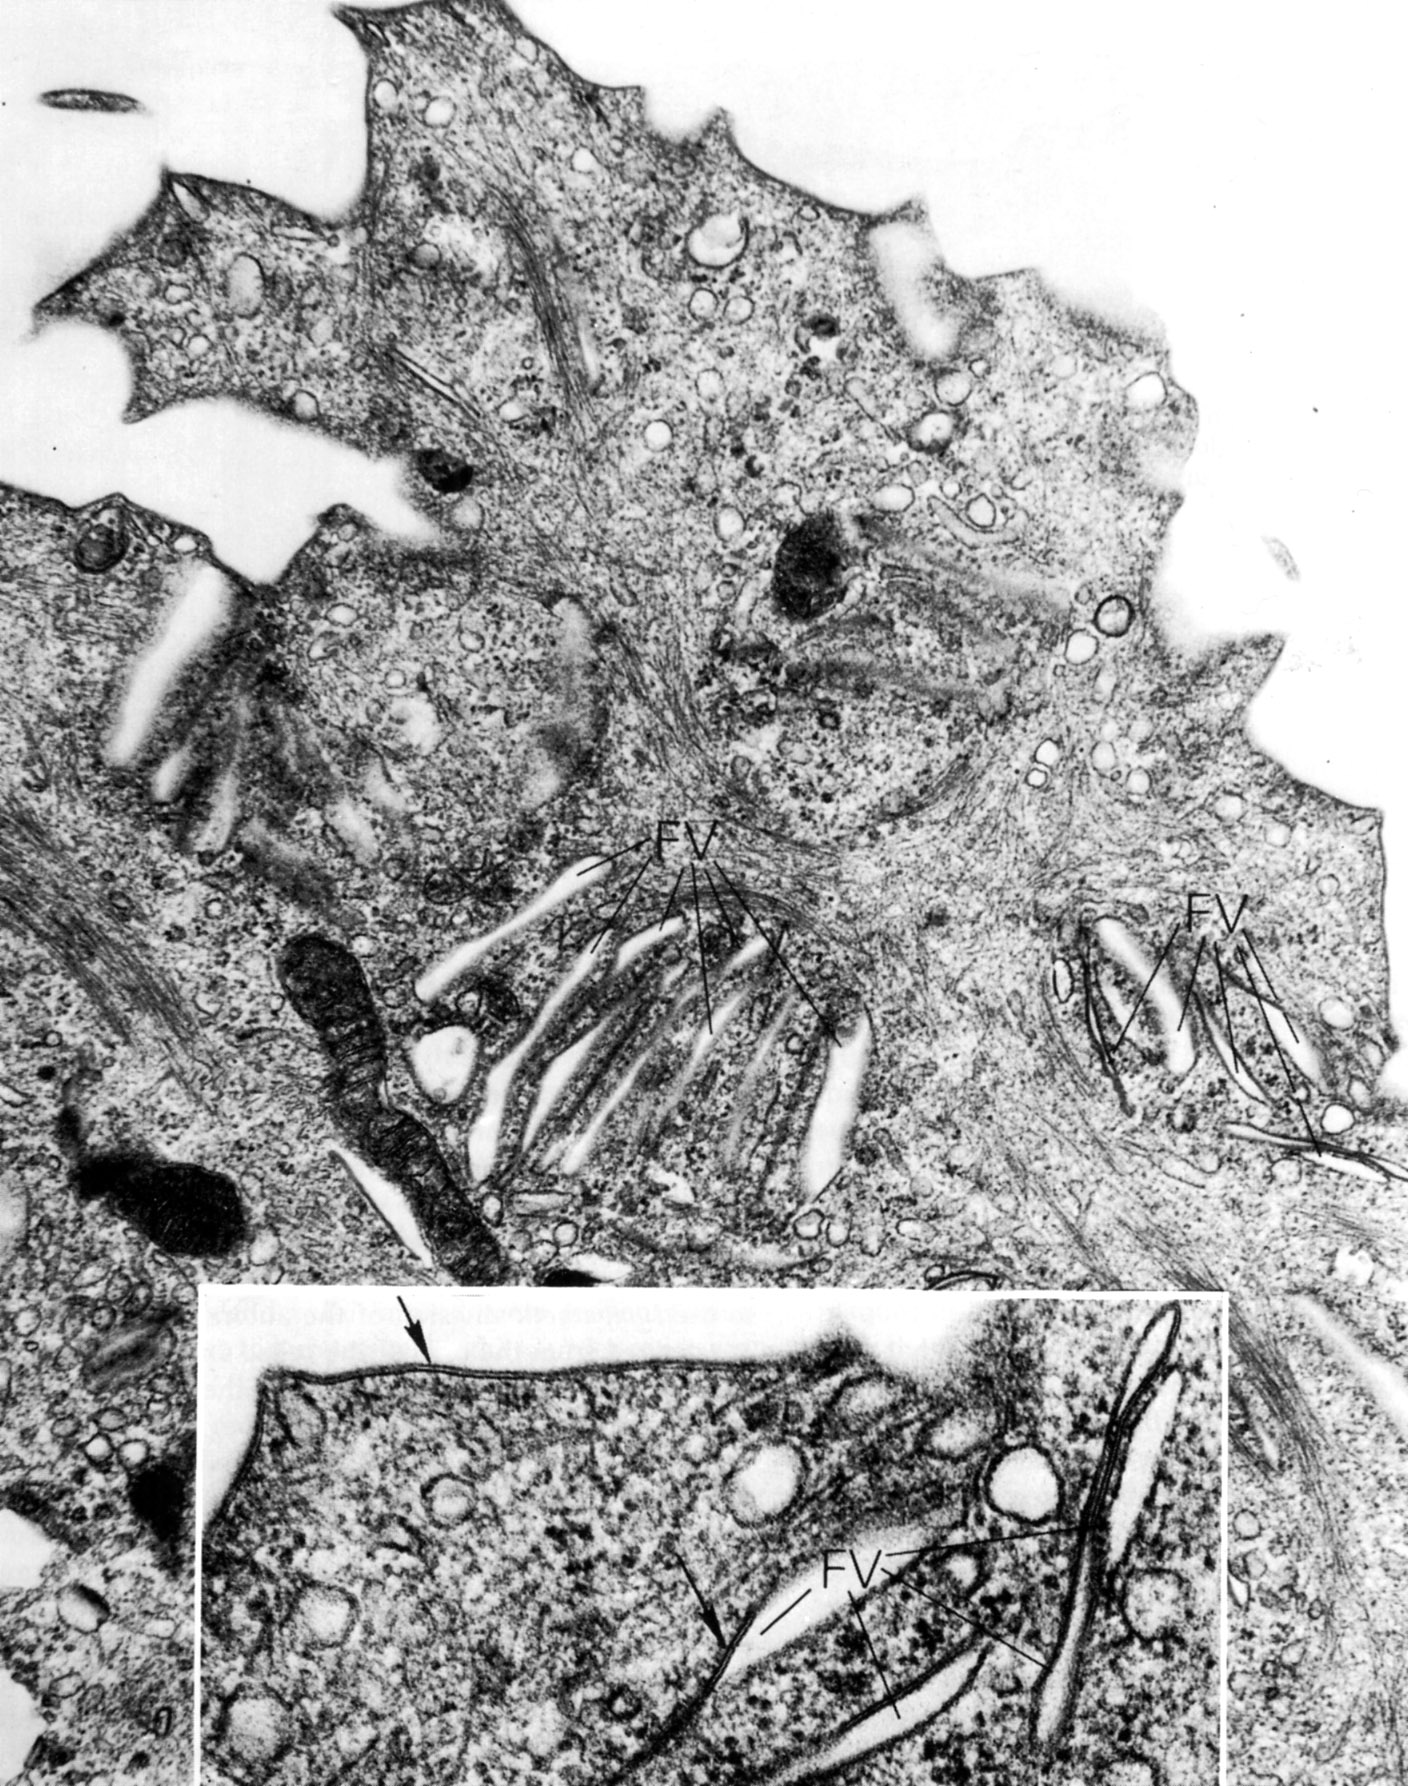

(flat) urothelial carcinoma in situ is covered. Transitional cell carcinoma (tcc), also called urothelial cell carcinoma (ucc), is the most common primary malignancy of the urinary tract and may be found along its entire length, from the renal pelvis. The transitional epithelium that lines most structures of the urinary tract —called also uroepithelium. Histology of transitional epithelium or urothelium in 3 minutes or less.